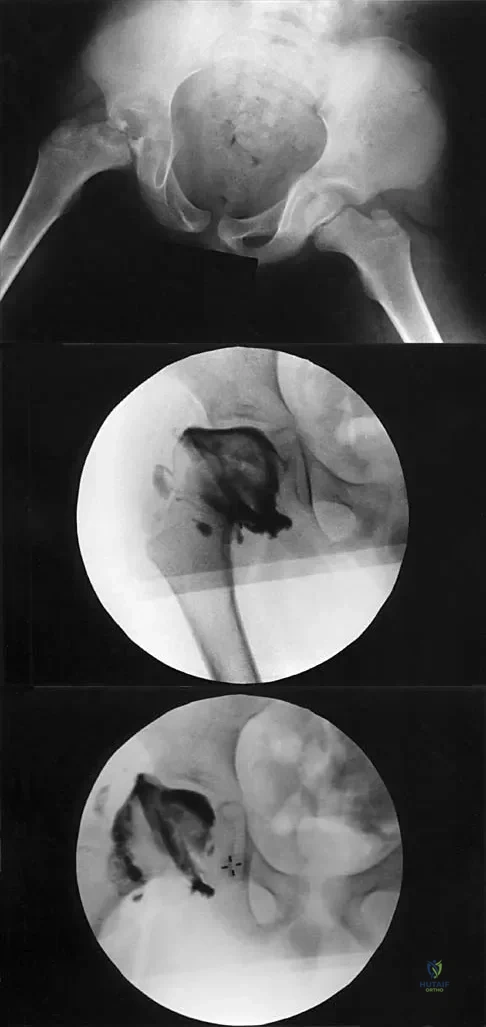

A 7-year-old patient has had a painless limp for several months. Examination reveals pain and spasm with internal rotation, and abduction is limited to 10 degrees on the involved side. Management consists of 1 week of bed rest and traction, followed by an arthrogram. A maximum abduction/internal rotation view is shown in Figure 40a, and abduction and adduction views are shown in Figures 40b and 40c. The studies are most consistent with

Explanation

The radiographs show classic hinge abduction. The diagnostic feature is the failure of the lateral epiphysis to slide under the acetabular edge with abduction, and the abduction view shows medial dye pooling because of distraction of the hip joint. Persistent hinge abduction has been shown to prevent femoral head remodeling by the acetabulum. Radiographic changes are characteristic of severe involvement with Legg-Calve-Perthes disease.The Catterall classification cannot be well applied without a lateral radiograph, but this degree of involvement would likely be considered a grade III or IV. Because the lateral pillar is involved, this condition would be classified as type C using the Herring lateral pillar classification scheme.

- Reinker KA: Early diagnosis and treatment of hinge abduction in Legg-Perthes disease. J Pediatr Orthop 1996;16:3-9.